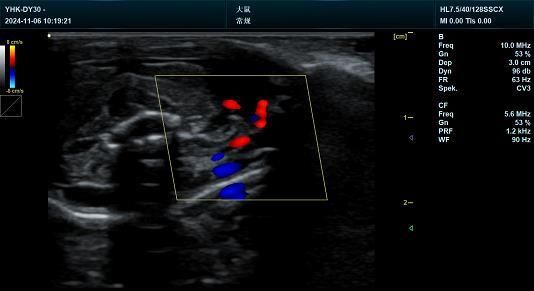

动物彩色多普勒超声诊断系统 YHK-DY30 技术参数一、设备名称:动物彩色多普勒超声诊断系统二、设备型号:Y...

设备名称:动物彩色多普勒超声诊断系统 设备型号:YHK-DY30 设备用途说明 主要用于犬、猫、小鼠、大...